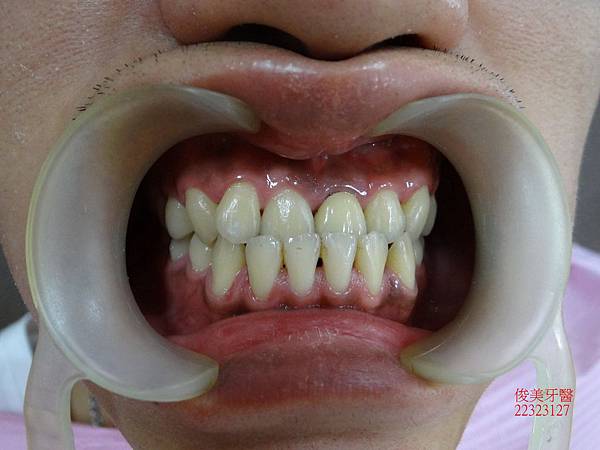

咬合狀況。

上排牙明顯被下排牙齒限制住。